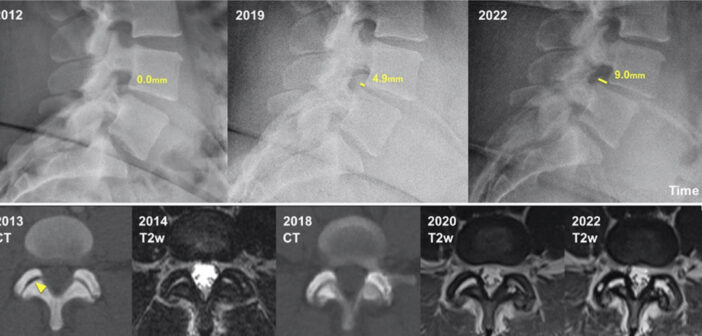

Evolution of lumbar degenerative spondylolisthesis with key radiographic features